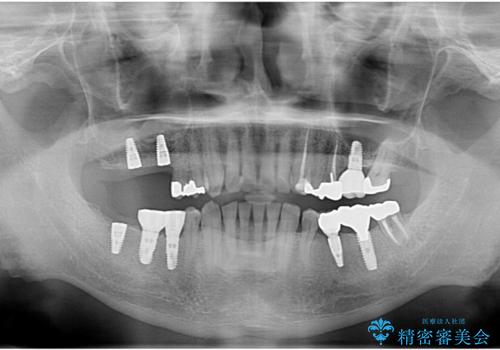

- 他院で奥歯が割れている為抜歯が必要と言われたとのことで来院。

右上56および左下5は割れていたためやむなく抜歯しインプラントにしていきました。

左下7(一番奥の歯)は抜歯をせずに済みましたが、高さがないため上の歯を矯正治療で沈め、また、歯ぐきの手術を合わせて行いクラウン(被せ物)をしっかり入れる処置をおこなっています。